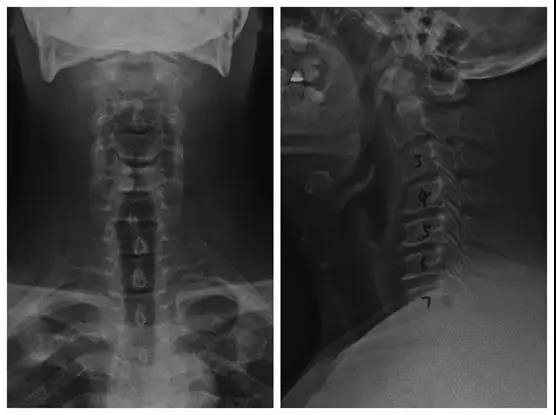

颈椎前路ACDF手术(零切迹固定融合器)

患者:男,51岁

主诉:双上肢麻木、疼痛一月,加重伴行走不稳3天

既往史:个人史及家族史无特殊

体征:

1.椎间孔挤压试验双侧+;

2.双前臂尺侧、双侧小指、环指、中指、皮肤感觉减退,右侧为著;

3.肱三头肌左/右=IV+/IV-,指屈肌左/右=IV+/IV-,小指展肌肉=IV+/IV-,右下肢肌力约IV+,左下肢肌力基本正常;

4.双侧Hoffmann征+,右侧Babinski征+,左侧未引出。

诊断:

1.颈椎间盘突出症(C6/7);

2.混合型颈椎病。

术前X线

术后X线正侧位片